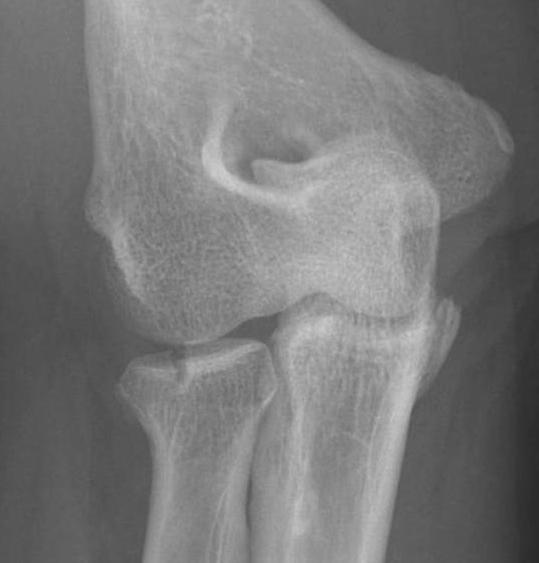

Complex Elbow Dislocation APComplex Elbow Dislocation Lateralelbo dis

Definition

Elbow dislocation with radial head fracture + coronoid fracture + MCL tear